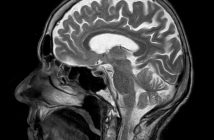

В научном мире произошёл настоящий прорыв — группе исследователей из Фуданьского университета в Шанхае впервые в истории удалось успешно заморозить и разморозить образцы мозговой ткани человека без каких-либо повреждений. Результаты эксперимента, опубликованные в авторитетном журнале New Scientist, открывают поистине фантастические перспективы, вплоть до возможности погружения людей в состояние криогенного сна.

Руководитель исследования Чжичэн Шао и его коллеги вырастили из стволовых клеток человеческого эмбриона самоорганизующиеся образцы мозга, известные как органоиды. Затем учёные поместили эти крошечные, размером всего 4 миллиметра, кусочки мозговой ткани в различные химические соединения, которые, по их предположению, могли бы помочь сохранить жизнеспособность клеток в процессе замораживания и последующего оттаивания.

Ключом к успеху стала уникальная смесь под названием MEDY, состоящая из метилцеллюлозы, этиленгликоля, диметилсульфоксида и соединения Y27632. Обработанные ею нейроны и стволовые клетки мозга показали минимальную гибель и продолжили нормально расти и функционировать после 18 месяцев глубокой заморозки!

Но учёные на этом не остановились. Следующим этапом стали эксперименты с замораживанием кубиков настоящей человеческой мозговой ткани, взятой у 9-месячной девочки, страдающей эпилепсией. И вновь успех — после разморозки структура образцов полностью сохранилась, а электрическая активность нейронов продолжалась как минимум две недели.